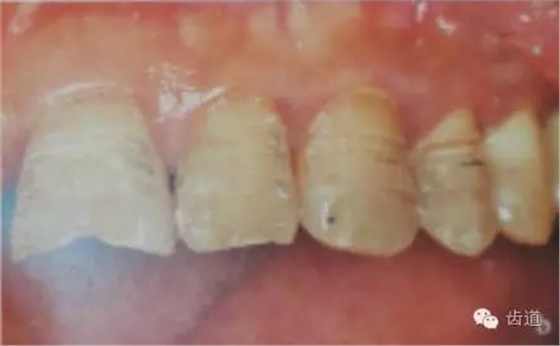

1、唇面預(yù)備:先用定深車針定出定深溝,再換合適車針磨除剩余的釉質(zhì)。

唇面磨除的量依據(jù)所用貼面材料及牙齒的變色程度而定。

如下圖:

3、切緣預(yù)備:瓷貼面的三種類型不同就是切端預(yù)備形態(tài)的不同:

1)開窗型:保持切端完整,沿切緣上緣制備出邊緣;

2)對接型:將患牙切端均勻去除0.5-1.0mm;

3)包繞型:在對接型的基礎(chǔ)上再于切端舌腭側(cè)制備并形成0.5-1.0mm深的無角肩臺(tái)。